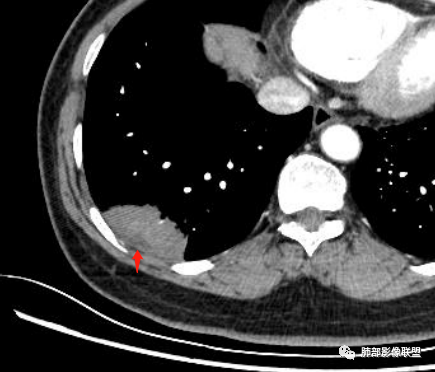

我觉得这个有价值。这不是胸膜,是肺内病灶的

南边:

这一条可能是胸膜

马春平(张家港市一院胸外科):

是的,病灶远端增厚水肿的脏层胸膜